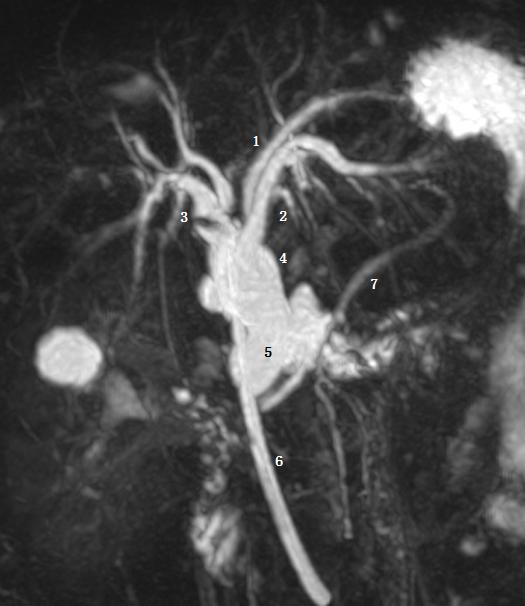

Ⅵ型为 2、3 段分级肝管汇入右肝管或肝总管。图为胆总管末端梗阻 T 管引流术后。图示 1 为 2 段肝管,2 为 3 段肝管,3 为肝右肝管,4 为肝总管,5 为胆总管,6 为 T 型管,7 胰管。